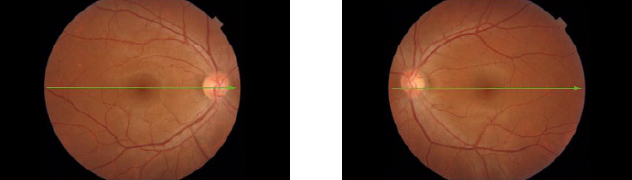

- 一般的な人間ドックの眼底写真

眼底カメラ。おおまかな情報はわかるが詳細まではわからない。

- 当院の眼科ドック

三次元眼底像撮影装置DRI OCT Triton、および前眼部光干渉断層計。緑内障、加齢黄斑変性、糖尿病黄斑浮腫、黄斑前膜、高度な乱視や白内障など、幅広い病気に対して強力に威力を発揮する。